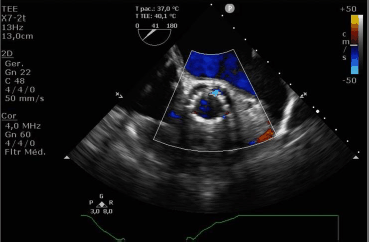

Paciente homem, 85 anos, portador de estenose aórtica grave e alto risco cirúrgico, submetido a implante valvar aórtico percutâneo (TAVI). Imediamente após a liberação da válvula, foi submetido a ecocardiograma transesofágico que mostrou leve refluxo.

A seguinte imagem foi obtida.

Nesse caso, nota-se regurgitação